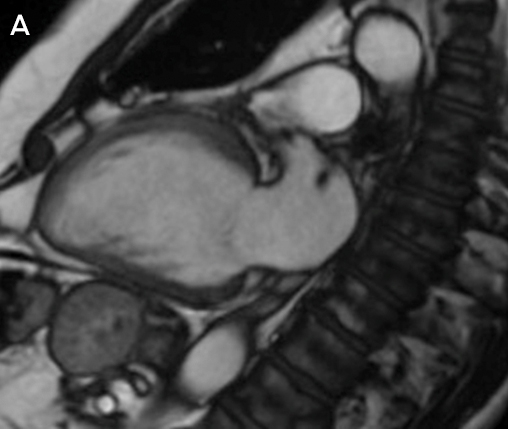

Clinical vignette 3: A 74-year-old man with a late-presentation ST-elevation myocardial infarction is shown to have an occluded left anterior descending artery during coronary angiography. Echocardiography shows an ejection fraction of 40%. Cardiovascular magnetic resonance (CMR) demonstrates that the anterior wall is akinetic, with full thickness infarction and no residual viable myocardium. Based on this information, he does not undergo stenting or coronary artery bypass graft surgery and is treated medically with heart failure therapy.

CMR imaging: two-chamber view showing a dilated left ventricle with akinetic anterior wall (A), and post-contrast imaging showing full thickness infarction of the entire anterior wall with no residual viable myocardium (B, arrows).